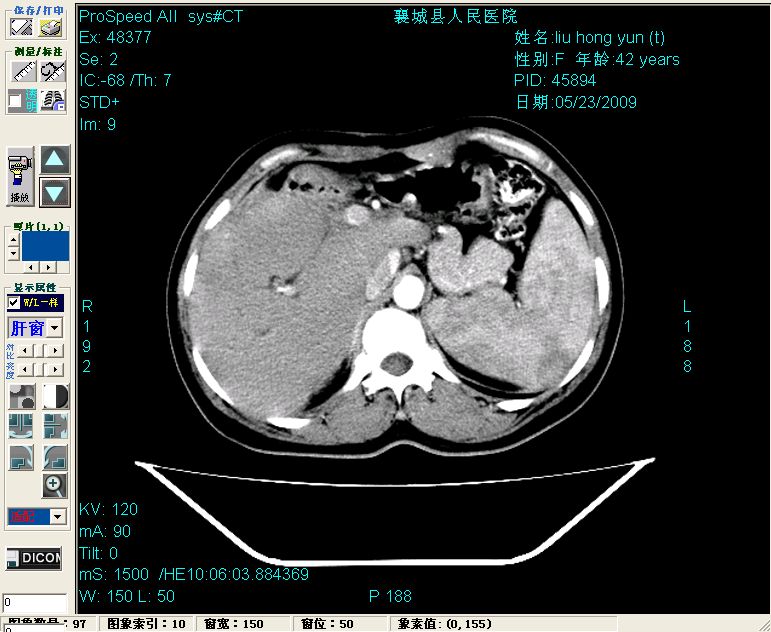

增强:

增强动脉期前述低密度区轻度早其强化,门脉期强化程度显著增高,延期扫描强化程度下降,但仍为相对高密度影

胰头部见结节状高密度影,其前方略可分辨扩强胆部管,平扫到增强始终有,但现在尚难与胃肠造影剂鉴别.

胆总管末端结石伴肝内胆管扩张合并结石!另:不除外合并胆系感染!

1)肝内胆管结石,胆总管末端结石伴肝内胆管扩张。2)肝左叶及肝右叶前段增强前后之异常表现,考虑炎性改变,不排除胆管细胞癌。

1)肝内胆管结石,胆总管末端结石伴肝内胆管扩张。2)肝左叶及肝右叶前段增强前后之异常表现,考虑炎性改变,不排除胆管细胞癌。3)脾大。